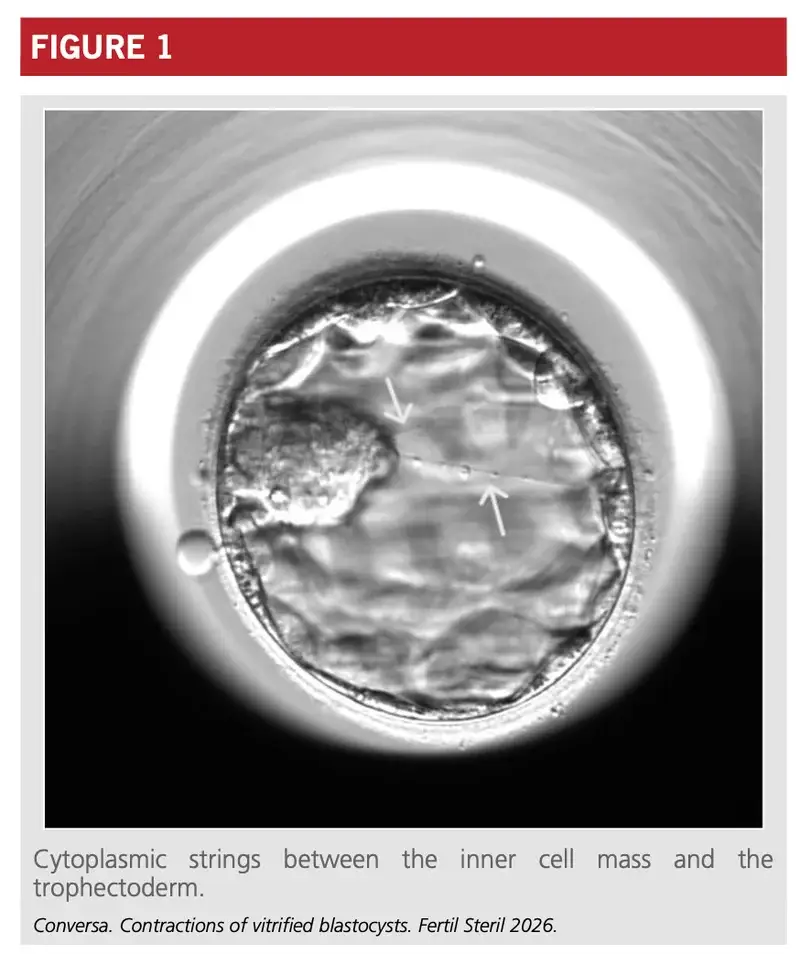

細胞をつなぐ架け橋「cytoplasmic strings」

Figure 1でも示されている「cytoplasmic strings(細胞質糸)」の存在は見逃せません。これは細胞間をつなぐ細い糸のような構造です。

- 役割: 細胞同士のコミュニケーションや構造の維持に関与

- 結果: この構造が確認できる胚は、着床率が有意に高い傾向

これらの微細な構造や動きは、これまでの「静止画によるグレード評価」では決して捉えることができなかった、胚の「内なる生命力」の証と言えます。